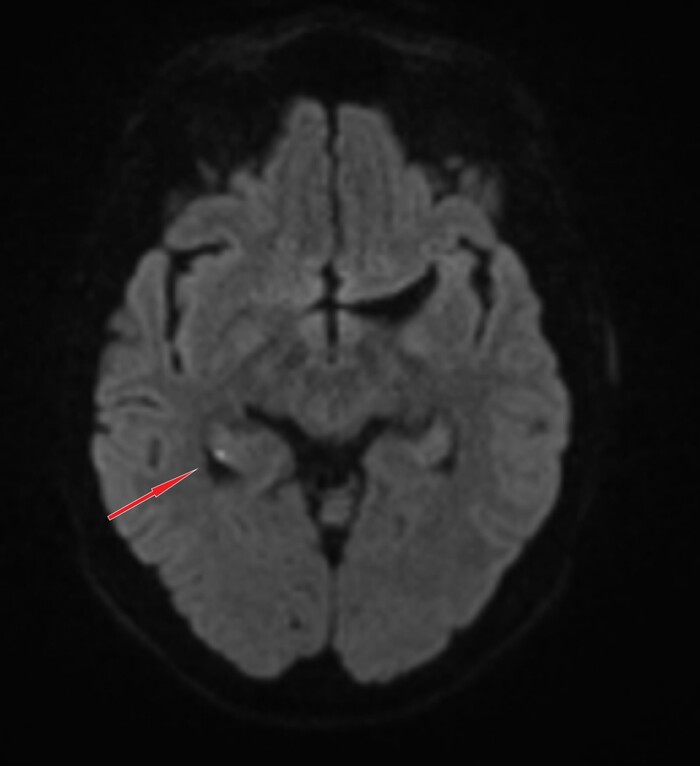

КТ-диагностика не показала каких-либо значительных объясняющих клинику изменений, только неспецифические кальцинаты в базальных ядрах (1) и обызвествление шишковидной железы (2), что соответсвует возрастной нормe:

На МРТ ангиография артерий головного мозга без патологии:

Само МРТ головного мозга тоже особых изменений не выявило, за исключением "светящейся точки" на DWI-изображениях с коррелатом на диффузионной карте:

что встречается при транзиторной глобальной амнезии (ТГА):

Kлинический синдром, характеризующийся внезапно возникшим эпизодом амнезии (антероградной, частично ретроградной), продолжительностью менее 24 часов без каких-либо других неврологических симптомов. В большинстве случаев симптомы полностью исчезают в течение нескольких часов после появления.